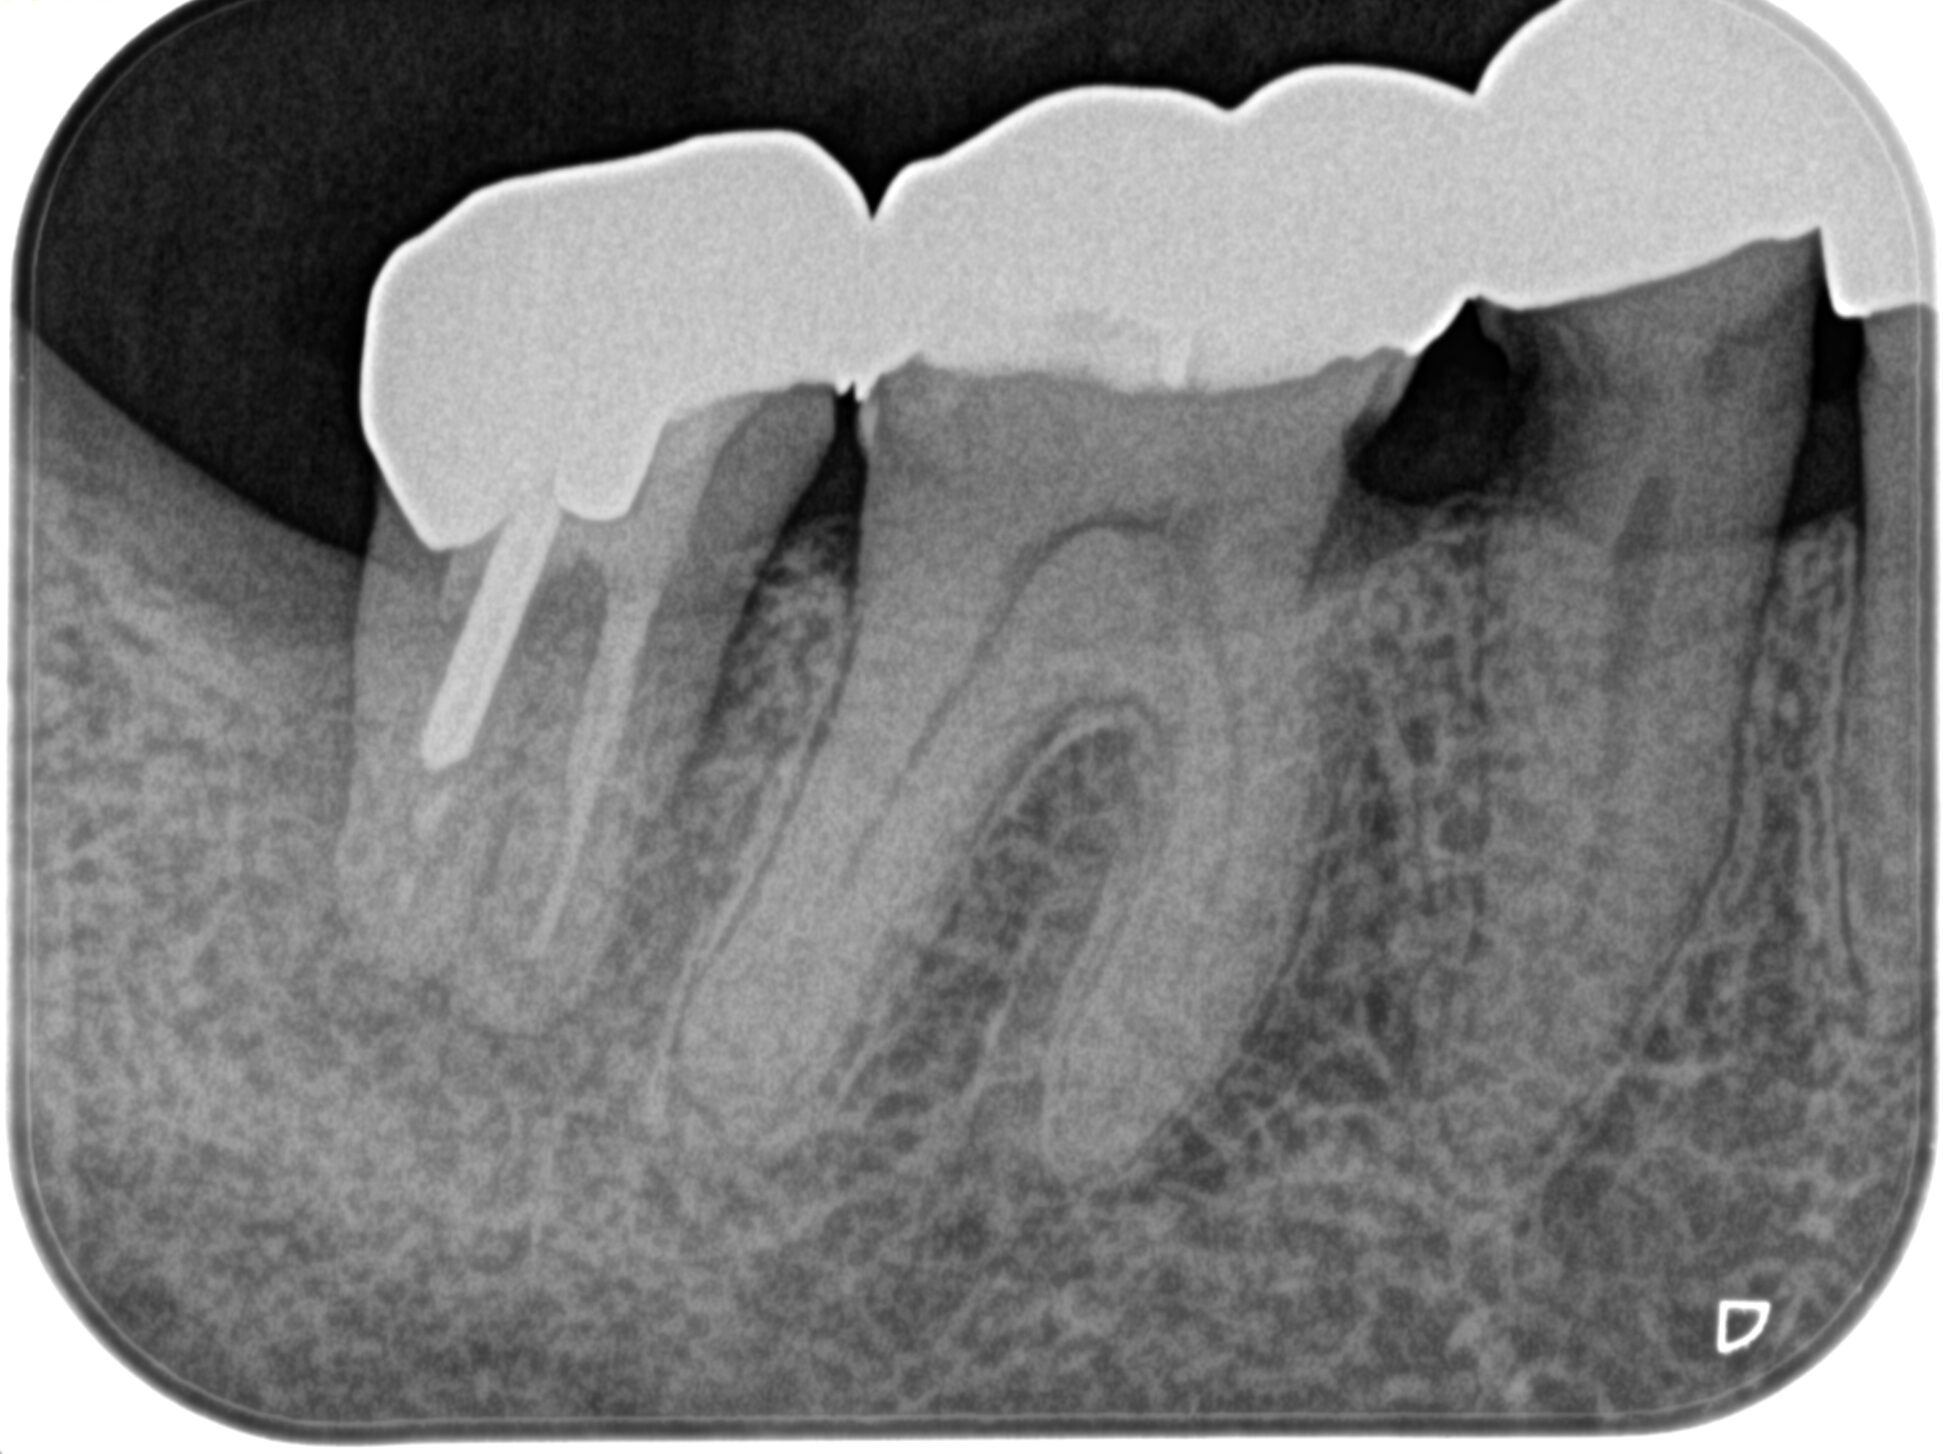

PA(2025.5.19)

確かに…

折れていると言われかねない状況だ。

が、何度も言うが

歯牙が折れているかどうか?は、その歯を抜歯して口腔外に出して直視しないとわからない

のである。